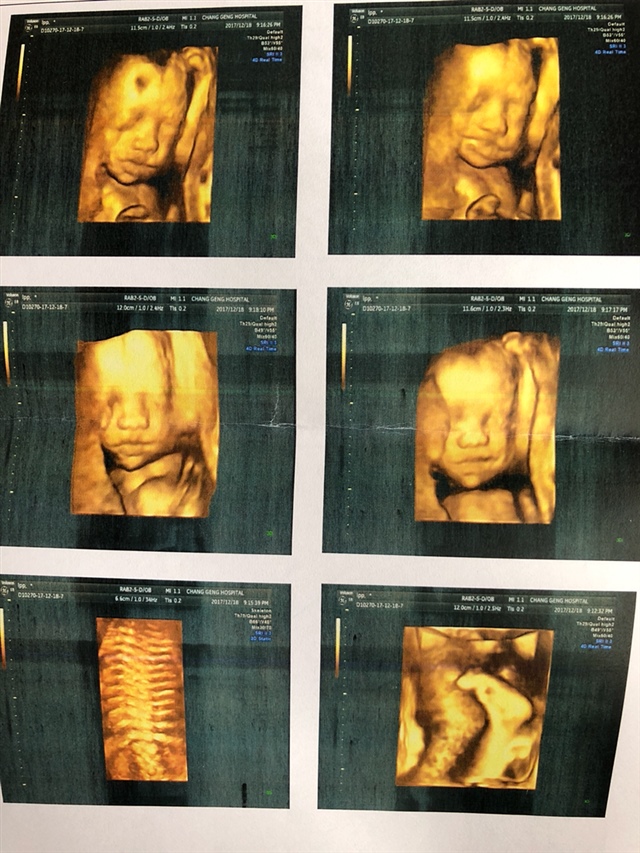

孕15周+5天